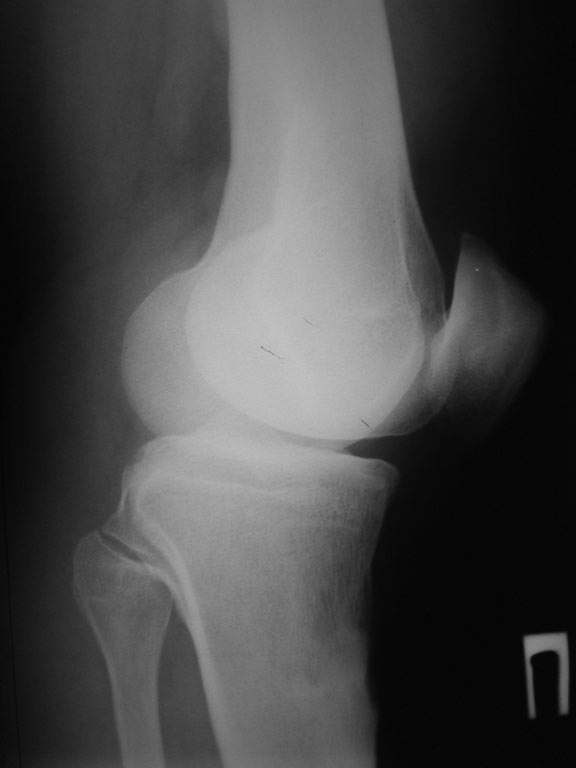

Уважаемый доктор Зайцев! Причина деформации проксимальной тибии у Вашего пациента - преждевременное и несимметричное закрытие зоны роста передней части проксимальной ростковой зоны б/б кости в следствии окультной травмы произошедшей в возрате 10-12 лет. Есть 2 причины рекурвационной деформации в области коленного сустава - мягкотканевая и костная.В данном случае Вы имеете дело не с рукурвацией коленного сустава, а с рекурвационной деформацией проксимальной голени. "Заднего выдвижного положения" на самом деле нет.То, что Вы видите на боковом снимке - это не задний подвывих голени - это снимок, сделанный в сгибании коленного сустава. Дело в том, что костные дефорсации в области коленного хорошо компенсируются за счёт движения в суставе. поэтому то, что вы видите, как задний подвывих на самом деле - сгибательное положение колена.

Это можно проверить очень просто - надо сделать стресс рентгенограмму в положении полного разгибания коленного сустава.Для этого посадите больного на стул, пятку поставьте на другой стул, дайте пациенту кассету 30Х40 держать с наружной стороны колена, и попросить ренгентехника сделать латеральный снимок с втутренней стороны. Сделав снимок здорового колена, Вы сможете расчитать деформацию.

10.-Рассмотрим представленную деформацию в боковой рентгенологической проекции.

Несложные расчеты на изготовленной скиаграмме (см. рис.1 ) показывают ,что суставная поверхность проксимального отдела б/б кости, находится в положении сгибания примерно 30 гр. Плоскость деформации лежит в сагитальной плоскости. Истинный угол деформации равен примерно 15 гр., с вершиной на 4-4.5 см. (примерно) дистальнее края суставной поверхности.

Вам представленна склаграмма боковой R – гр болного вынесенного на обсуждение.

А – ось бедра.

Б – линия Blumensaat/

В – имеющаяся линия суставной поверхности б/б кости.

Г – положение суставной поверхности в норме, по отношению к продольной оси б/б кости.

Д – продольная ось голени.

86 гр. (Г-Д) отношение суставной полверхности к оси голени.

~ 30 гр. – положение сгибания.